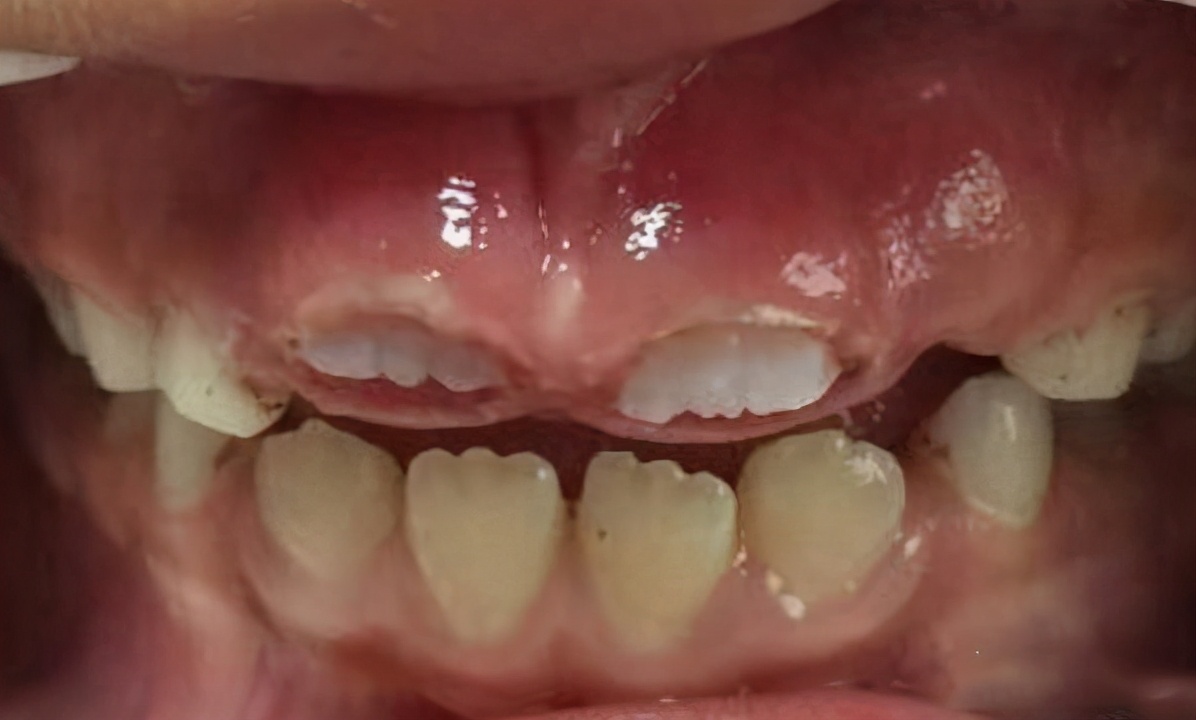

2、牙龈增厚

这是因为乳牙过早脱落,导致牙龈长期受到咀嚼摩擦而变厚变硬,这就是牙龈增厚。打个比方,本来欣欣的乳门牙要在7岁时自然掉落,但是在她6岁的时候因为摔跤意外把门乳牙磕掉了,而正常恒门牙需要到7岁才能萌出,那么在这一年时间里,欣欣长门牙的地方就会一直空着,吃东西咀嚼会摩擦裸露的牙龈导致其变厚。等到恒门牙要长出来的时候,因牙龈太厚太硬就难以长出,这时就需要切开增厚的牙龈,帮助新牙长出,这就叫微创开窗助萌术。